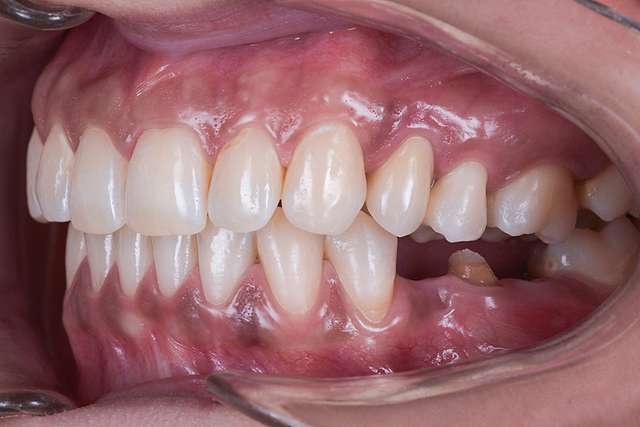

Guided surgery, for one, facilitates an ideal pre-planned position, in relation to available bone, and even more important, in relation to the future implant supported crown. Guided surgery translates into increased precision, which means safer surgeries, reduced surgery time, and reduced trauma. Also the focus of these types of treatments is shifted towards tissue reconstruction, which on the long run, has a far greater impact esthetically and biologically. Tissue stability means implant longevity. This case is a relevant example for this type of approach towards implant dentistry.